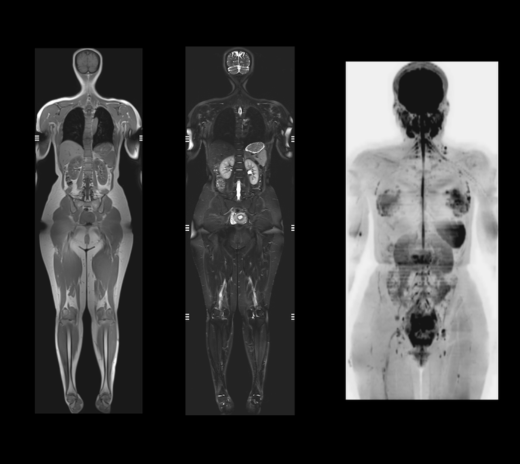

磁力共振扫描影像(全身)